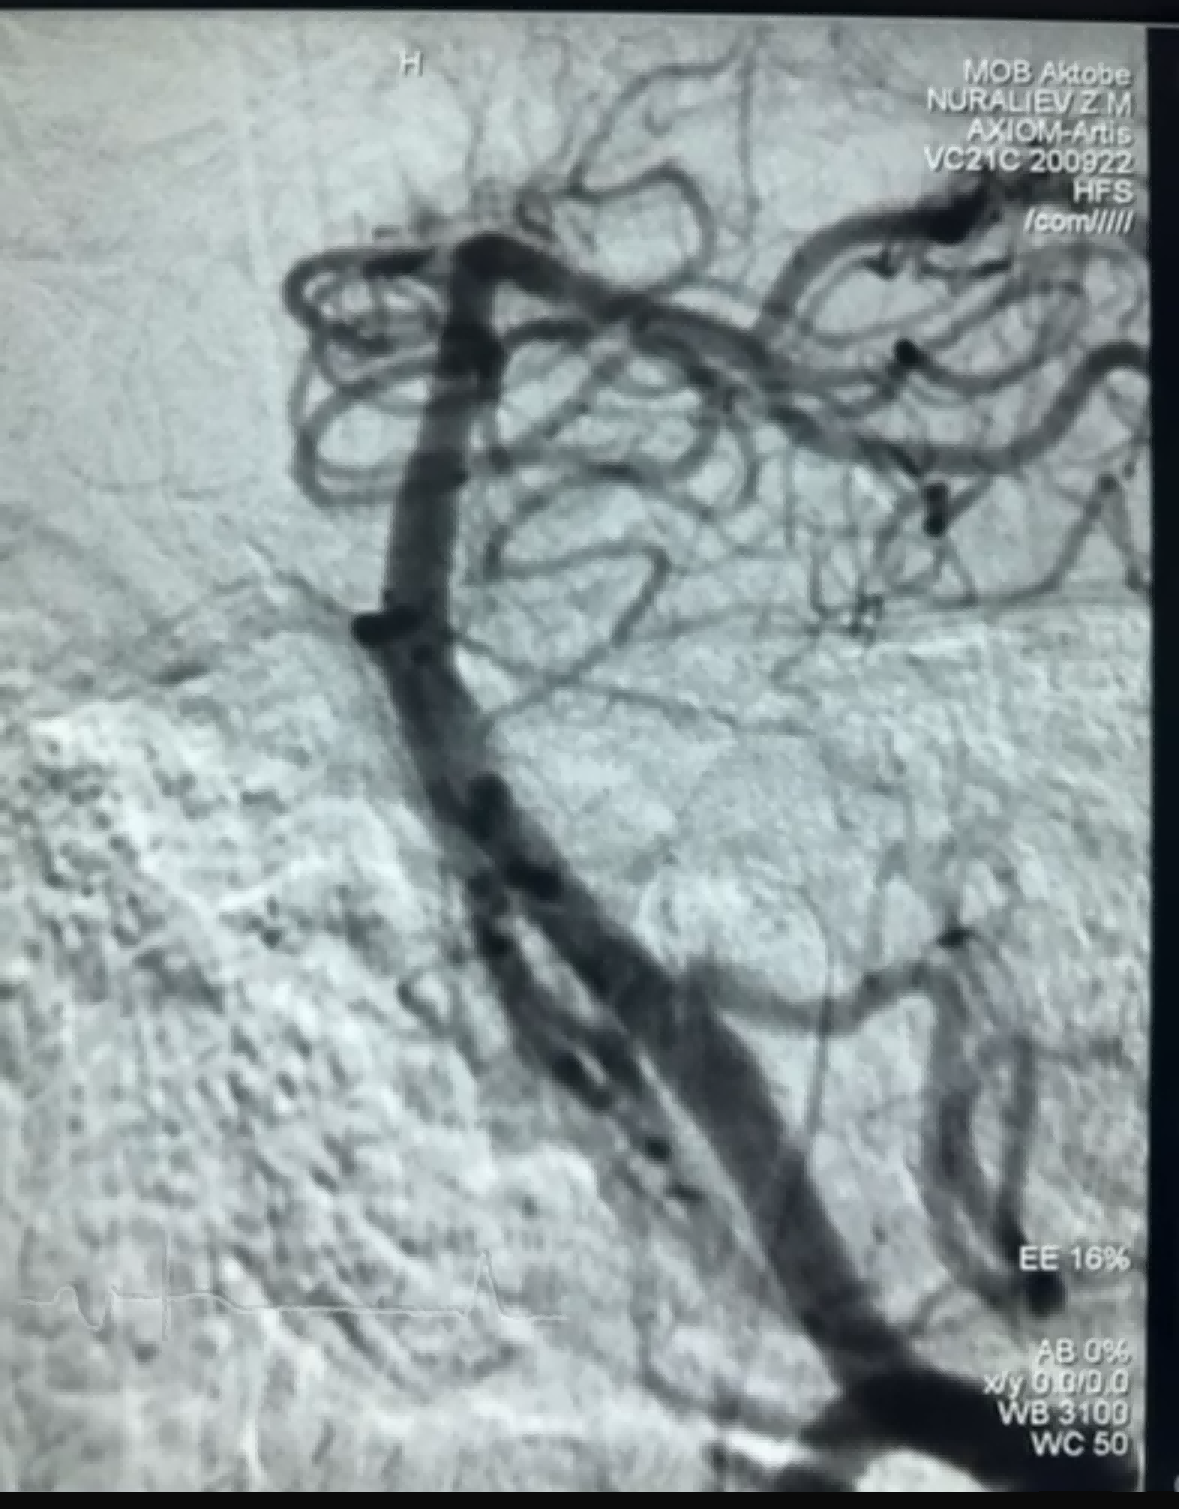

Recientemente, hubo un caso exitoso de trombectomía utilizando el Dredger Stent Retriever de NeuroSafe Medical Co., Ltd. El Dredger Stent Retriever tiene una punta suave no invasiva, que reduce en gran medida el riesgo de daño íntimo, y tiene un diseño de orificio especial único que captura coágulos de sangre principalmente al sujetar los cambios de espacio.